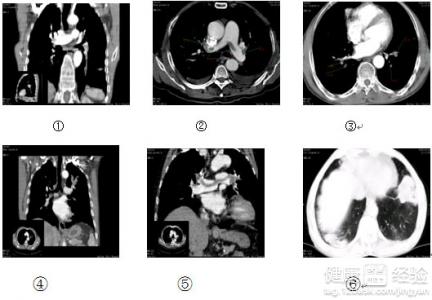

動脈栓塞,是指血塊或者進入血管內的異物稱為栓子,隨著血流的停頓在口徑相似較小的的周圍動脈或者內髒動脈的動脈內,造成血流障礙。動脈栓塞,一般是由於栓塞、血管收縮、血管痙攣、動脈瘤引起。動脈栓塞主要是因為血栓導致,除此之外,腫瘤、空氣、脂肪等異物也有可能會成為栓子。血栓大部分會來源於心髒,經常見於風濕性心髒病、心房顫動和心肌梗塞等。血栓所導致的栓塞,經常發生於心血管病人。

2動脈栓塞的發病症狀。動脈栓塞的早期症狀是間歇性跛行,遠側動脈博動減弱或者消失。疼痛可能會發生在下腰,臀、髂、大腿後側或小腿腓腸肌部位;還會發生與小腿肌群,在肢體慢性缺血時,皮膚萎縮變薄、發亮等。

3動脈栓塞的治療方式。非手術治療,主要目的是減低血脂和血壓,接觸血液的高凝狀態,促使側枝循環形成;手術治療有經皮腔內血管成形術,內膜剝脫術,旁路轉流術等。對於動脈栓塞要積極控制易發源,具有良好的預防作用。